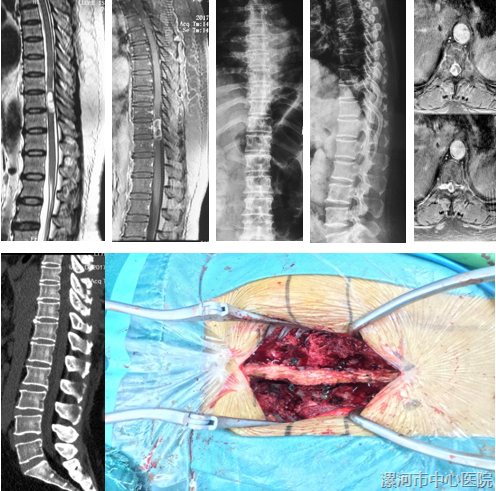

病例4:L3-4椎管内肿瘤

所有病例肿瘤切除完整,手术时间56~142min(77.1±21.6min),术中出血量110~370ml(217±42.6ml)。

2例出现脑脊液漏,未出现脊髓损伤、感染等相关并发症,随访12~28个月(17.2+8.1个月)。

术后1年JOA评分由术前(12.2±2.3)分上升至(23.7±3.8)分,差异有统计学意义(P<0.05)。

末次随访时,X线片提示脊柱无椎体滑脱,CT评估椎板无移位及继发椎管容积减小;MRI显示肿瘤无复发。